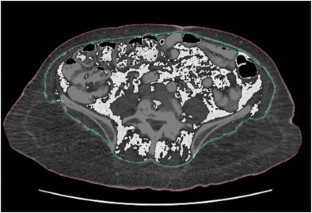

Retrospective review of patients undergoing elective colectomy for cancer at a single tertiary-care center from 2010 to 2016. Adipose tissue distribution measurements, including visceral fat area (VFA), were determined from preoperative imaging. The primary outcome was 30-day postoperative complication; secondary outcomes included overall and disease-free survival. Multivariable logistic regression was performed to determine association between obesity metrics and outcome.

Two hundred and sixty-four patients underwent 266 primary resections of colon cancer. Twenty-eight patients (10.5%) developed major morbidity (Clavien-Dindo grade ≥ III). VFA but not BMI was significantly associated with morbidity in multivariate analysis (p = 0.004, odds ratio 1.99, 95% confidence interval 1.25–3.19). No other imaging-derived anthropometric was associated with increased morbidity. In receiver operating characteristic analysis, VFA was predictive of major morbidity (area under curve 0.660). A cutoff value of VFA ≥ 191 cm2 was associated with 50% sensitivity and 76% specificity for predicting major morbidity. Patients with VFA ≥ 191cm2 had 19.4% risk of morbidity, whereas those with < 191 cm2 had 7.2% risk (relative risk ratio 2.69, unadjusted p = 0.004). Neither VFA nor BMI was associated with overall or disease-free survival.